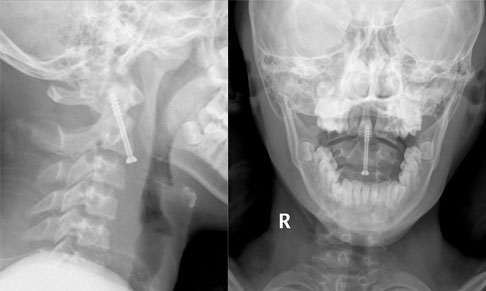

病例4  寰枢椎复合骨折,后路颈1-3椎弓根螺钉复位固定术。

患者17岁,男性, 寰枢椎复合骨折并脱位。

患者受伤2天入院,四肢肌力正常。

患者术后四肢肌力正常,术后骨折解剖复位。